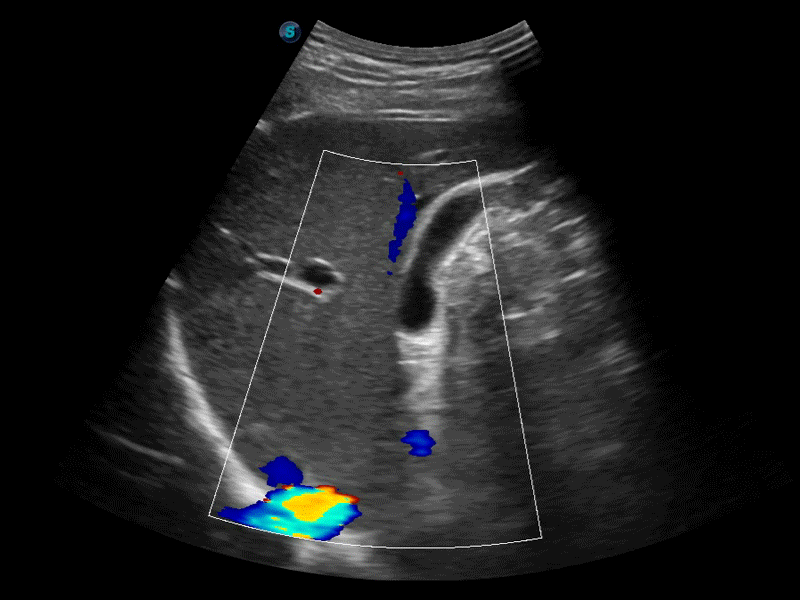

临床图像

• SR Flow高分辨率血流成像技术

高分辨率血流成像技术提高了对低速血流信号的检测能力。在提高空间分辨率的同时,也克服了血流外溢现象,为用户提供更加真实的血流动力学信息。